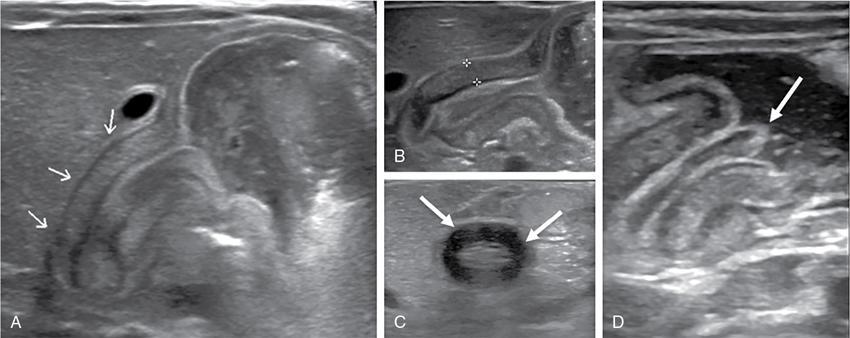

C.V. Kanimozhi, S. Muralinath, Raveendran J. Many of the important congenital gastrointestinal abnormalities present acutely in the newborn; some present much later. These include obstructive gastrointestinal lesions that present with vomiting, abdominal distension and not having passed meconium. The imaging modalities that are most commonly used in the evaluation of neonatal gastrointestinal abnormalities are plain films, contrast studies and ultrasound. Plain films remain a valuable tool in the assessment of abdominal abnormalities in the neonate. They are also an excellent guide to determining the next proper imaging study to perform for a particular problem. Certain neonatal bowel disorders have a pathognomonic appearance on radiographs obviating the need for further imaging. The essential and basic view to be done at the bedside is the supine view of the abdomen. In the evaluation of abnormal intra-abdominal gas patterns, alternative decubitus views, prone and supine cross-table lateral views may be taken. Erect view is not utilized in neonatal practice at the bedside as it is impossible to restrain a neonate in that position and unnecessarily subjects the neonate to stress, which may worsen the condition of an already sick baby. Evaluation of the bowel gas pattern and the anatomic localization of the intra-abdominal gas is the key to diagnosis in the evaluation of diseases of the GI tract. The bowel gas in the neonate is essentially swallowed air (Box 7.8.1). Movement of Air Through the GIT in a Term Neonate Most infants pass meconium by 24 hours of life. In order to interpret the bowel gas pattern and determine if an abnormality is present, it is crucial to know the age of the neonate (hours since birth) at the time the radiograph was taken. When there is impaired swallowing, such as due to CNS depression or in prematurity, radiographs show diminished bowel gas. In cases of bowel atresia, radiographs show absence of bowel gas in distal segments. Thus, the distribution of bowel gas and its pattern serve as pointers to the diagnosis. After the radiograph has been done, depending on the findings, an ultrasound or fluoroscopic contrast study may be performed next. The radiologist should tailor the contrast study to suit the particular patient and the clinical question that needs to be answered. In cases of suspected high GI obstruction, an upper GI contrast series is study of choice; in cases of suspected low GI obstruction a contrast enema should be performed to delineate the anatomy. When performing fluoroscopic studies, it is important to bear in mind the radiation dose and to adopt the ALARA principle. Minimizing radiation exposure in children is important because they are more sensitive to the effects of radiation and have a longer life expectancy than adults. The technical parameters must be adapted to paediatric imaging. Ultrasound is a useful bedside tool particularly in the sick neonate. In neonates, the sonographic image resolution is excellent due to the lack of significant body fat. In neonates, exquisite images of the abdomen can be obtained with the high-resolution ultrasound probe, which permits imaging the bowel wall in great detail. In addition, it can also reveal other causes for abdominal distension or vomiting. In this chapter, we will discuss the aetiology, clinical presentation and imaging appearances of congenital neonatal gastrointestinal abnormalities. We will also discuss common acquired abnormalities that present in the neonatal period, namely necrotizing enterocolitis. Congenital oesophageal malformations of the newborn include the various types of atresia (with and without fistula) and oesophageal duplications. Oesophageal atresia with or without tracheoesophageal fistula (TEF) is a common congenital anomaly that manifests in the neonatal period. It is also the most important congenital malformation of the oesophagus. Oesophageal atresia is commonly associated with other anomalies of the gastrointestinal tract such as imperforate anus, pyloric atresia, duodenal atresia and annular pancreas and less frequently with anomalies of the cardiac and genitourinary systems. About 20% of patients with oesophageal atresia have the VACTERL syndrome (vertebral anomaly, anorectal atresia, cardiac lesion, tracheoesophageal fistula, renal anomaly, limb defect). Oesophageal stenosis and webs may be associated with oesophageal atresia. The aetiology of oesophageal atresia and TEF is not completely understood. Faulty separation of the primitive trachea and oesophagus is the most widely accepted theory. The way the primitive foregut cleaves into a ventral (tracheal) passage and a dorsal (oesophageal) passage is a complex process and is poorly understood. Folds developing from the longitudinal ridge is said to separate the two. When the separation has an extreme tracheal bias, an oesophageal atresia occurs and if the bias is towards the oesophagus, then a tracheal atresia ensues. Incomplete separation may result in fistula of various types. Oesophageal atresia and TEF are classified depending upon the absence or presence and location of the fistula between the oesophagus and the trachea (Fig. 7.8.1). Neonates present within a few hours of birth with excessive salivation, drooling, cyanotic spells and regurgitation of feeds. The inability to successfully pass a nasogastric tube strongly suggests oesophageal atresia. Newborns with H-type fistula may have feeding difficulties and choking, but often the presentation and diagnosis is only later in infancy when the patient presents with cough, choking episodes and recurrent pneumonia. The role of imaging is to diagnose, define the anatomy to the best extent possible and evaluate for other anomalies to provide a clear picture for the paediatric surgeon. For example, it is important for the surgeon to know the side of the aortic arch in order to lateralize the surgical approach. Chest X-ray and Echo can localize the arch and determine if an anomalous right-sided aortic arch is present. Plain films of the chest including abdomen need to be obtained. The radiograph will demonstrate the air-filled distended proximal oesophageal pouch. If a nasogastric tube has been inserted, the coiled tube will be seen within the pouch. Absence of bowel gas in the abdomen indicates oesophageal atresia without a distal fistula – types A and B have this radiographic appearance (Fig. 7.8.2). The presence of gas in the gastrointestinal tract indicates the presence of a distal fistula – types C and D (Fig. 7.8.3). Contrast studies to delineate the proximal pouch are generally not indicated. Coiling of the nasogastric tube in the proximal pouch confirms the diagnosis. Chest radiographs frequently show changes of consolidation due to aspiration pneumonia, most often involving the right upper lobe (Fig. 7.8.4). In cases of H-type fistula, plain films are nonspecific and the diagnosis depends on contrast studies. Radiological diagnosis is made by means of a tube oesophagogram. This study has the potential risk of aspiration and the neonate may desaturate quite rapidly. Hence, it is important to have neonatal emergency resuscitation at hand. The tube oesophagogram is performed under fluoroscopy with the baby in lateral- or steep-prone oblique position. The NG tube is placed at the oesophagogastric junction and is gradually withdrawn while simultaneously injecting contrast. Nonionic low-osmolar contrast agent should be used. Most of the H-type fistulas are located in the lower cervical and upper thoracic regions with the fistula typically coursing upward and forward from the oesophagus. In the presence of a fistula, the contrast will be seen passing into the trachea in an upwardly oblique configuration. Aspiration during the study can also cause the contrast to appear in the tracheal tree and the lungs. It needs to be established whether the contrast has passed through the fistula or whether aspiration has occurred. Recording of the fluoroscopic run and reviewing the images may be required to make this distinction. Repeat examination may be required. Demonstration of H-type fistula can be difficult radiologically. In such patients, bronchoscopy with transfistula guidewire placement has been found to be of use. MRI – High resolution structural MRI is a new technique that is being used to visualize tracheobronchial anatomy. The disadvantage with radiographs is that one cannot determine the anatomic subtype of TEF, the site of the TEF or the length of the gap between the atretic segments. Using ultrashort echotime (UTE) MR imaging, it is possible to visualize the exact site of the fistula and assess the size of the oesophageal gap. This can aid presurgical planning and help identify infants at risk for complications, such as those with a long oesophageal gap. Imaging plays an important role in the evaluation of early and late complications of atresia repair. Early complications include anastomotic leaks and are seen in about 10%–20% of cases. Oesophageal contrast study, using a nonionic low-osmolar contrast agent, is performed to demonstrate the leak at the anastomotic site (Fig. 7.8.5). Leaks are associated with a greater incidence of subsequent stricture development. Anastomotic stricture is a common complication seen in about 30%–40% of cases. Often there is a slight narrowing at the site of repair without the patient having any difficulty in swallowing (Fig. 7.8.6). The anastomotic narrowing is clinically relevant only if the patient has dysphagia; such cases respond to dilatations. Recurrent TEF occurs in 5%–10% of cases after oesophageal atresia repair. Late complications include dysphagia, gastroesophageal reflux, tracheomalacia and chest wall deformities. Dysphagia can occur post-operatively due to abnormal oesophageal motility. Oesophageal dysmotility can be caused by abnormal neural development of the oesophagus or may result from complication of atresia repair. Gastroesophageal reflux affects 40%–65% of patients following oesophageal repair. It may be due to an intrinsic deficiency in the motor function of the oesophagus; this may get exacerbated postrepair due to an alteration of the anatomical gastroesophageal junction. Oesophageal atresia key imaging finding – X-ray shows NG tube coiled in proximal oesophageal pouch. The stomach is divided into the fundus and body proximally and the antrum distally. The antrum is divided by the sulcus intermedius into a proximal pyloric vestibule and a distal pyloric antrum or pyloric canal. This canal terminates into the pyloric sphincter beyond which is the duodenum. Congenital anomalies of the stomach that manifest in the neonatal period are uncommon. Hypertrophic pyloric stenosis (HPS) is the most common surgical cause of vomiting in infants. The incidence is 2–5 per 1000 live births, with geographic and racial variations. Compared to Caucasians, HPS is less common amongst Asian populations. The male to female ratio is approximately 4:1, occurring more commonly in the first-born child. The precise aetiology is unknown. Overactivity or prolonged spasm of the circular muscle of the pyloric antrum is thought to be the primary problem in these infants. This spasm leads to muscle hypertrophy and obstruction. Multiple hypotheses have been proposed for this prolonged spasm. One is that some infants are genetically predisposed to increased gastrin production which leads to a vicious cycle of hyperacidity, increased gastric contraction and secondary development of muscular hypertrophy. Most infants present after the first week of life and before 3–4 months of age. Typical symptoms include projectile nonbilious vomiting, regurgitation and difficulty in feeding. The gastric outlet obstruction can lead to emaciation. The distended stomach with active peristaltic activity may be visible through the thin abdominal wall. In the past barium upper GI series was the mainstay diagnostic tool for HPS. Prior to the barium study, the stomach may need to be decompressed via a nasogastric tube. The classic sign on a barium study is the ‘string sign’ (Fig. 7.8.7) produced by a thin stream of barium in an elongated narrowed pyloric canal; the canal typically curves upward. In severe cases, complete obstruction will lead to the ‘beak sign’, which is produced by beaking of the contrast as it enters the pyloric canal. With lesser degrees of obstruction, the ‘double track sign’ is seen. This is produced when the pyloric canal is flattened and the barium accumulates in the crevices along either side of the flattened canal. Pylorospasm can transiently mimic the findings of HPS. Currently, ultrasound is the modality of choice for the diagnosis of HPS and upper GI studies are seldom used. Ultrasound is considered the ‘gold standard’ as it allows direct examination of the pyloric muscle and also provides the ability to perform a dynamic study. The ultrasound examination is performed with a linear high-frequency transducer (6–10 MHz). The examination begins with the baby in supine position. First, the antropyloric region is identified; the pylorus is usually located medial and posterior to the gall bladder. The normal pyloric muscle is a thin hypoechoic layer that measures 2 mm or less. The abnormal pyloric canal shows thickening of the muscle and the mucosa to varying degrees. In cross section, it is seen as a hypoechoic structure likened to a doughnut. The length of the canal is measured in long section where its appearance is likened to the cervix. The sonographic diagnostic criteria for HPS are a thickened muscle layer measuring ≥3 mm and an elongated pyloric channel ≥15 mm (Fig. 7.8.8). The diameter of the pylorus in cross section was also one of the originally used measurements. However, due to a significant overlap between normal and abnormal, this measurement is no longer utilized. Additional ultrasound findings of HPS are hypertrophy of the pyloric mucosa and a distended, actively peristalsing stomach. The hypertrophied redundant mucosa projects into the antrum analogous to the ‘nipple sign’ in barium studies (Fig. 7.8.8D.). Colour Doppler imaging shows increased flow in the muscle and mucosa. The above-described measurements of pyloric muscle thickness and canal length are vital to diagnosis. However, dynamic assessment is equally important. One must evaluate the antropyloric region over a period of time to ensure persistent stenosis without evidence of relaxation and opening of the canal. A distensible antropyloric region with normal passage of gastric contents excludes HPS. Transient contractions of the pylorus or pylorospasm can mimic pyloric stenosis in both measurement and appearance. With observation over a period of time, opening of the pyloric canal may be visualized. Hence the key to diagnosis of HPS is persistent non-relaxing thickened musculature. Gas in the stomach may obscure the pylorus. To avoid this, place the infant in an oblique position, right side down which will allow the antrum to fill with fluid. Conversely, an overdistended fluid-filled stomach can displace the pylorus dorsally. In such cases, turning the infant left side down will displace the fluid towards the fundus and will allow the pylorus to rise to a more anterior position. At times, equivocal examinations may occur where the muscle measures 2–3 mm in thickness and does not relax. In these patients, careful monitoring with repeat ultrasound is warranted. In a few cases, the abnormalities advance overtime to fully developed HPS. Hence in such equivocal cases if vomiting continues, follow-up ultrasound is advisable. Surgical pyloromyotomy is the treatment for HPS. On ultrasound, the myotomy site can be seen as an interruption in the hypoechoic doughnut. It is important to be aware that postsurgery, the pyloric muscle may remain thickened for up to 5 months with a gradual return to normal thickness. In the first week after surgery, the muscle can be the same thickness as pre-op or even thicker. One should not be alarmed by this appearance. The dimensions gradually return to normal over the course of a few months. Postop if the child is thriving well, there is no need for imaging to be performed. HPS key imaging finding: On high-frequency ultrasound muscle thickness ≥3 mm and elongated pyloric channel ≥15 mm. Pyloric atresia is a rare anomaly comprising less than 1% of all intestinal atresias. Pyloric atresia is classified into three types (Fig. 7.8.9): The exact aetiology remains controversial. In the past, it was postulated that failure of recanalization of the gastrointestinal tract was the cause. Recent evidence suggests that pyloric atresia is the result of localized vascular occlusion. This vascular theory suggests that the atresia is due to focal ischemia secondary to intrauterine stress, vascular insult or anoxia. In complete obstruction, the presentation is in the neonatal period with nonbilious vomiting within the first few hours of life. Incomplete obstruction due to a diaphragm has a variable presentation depending on the size of the orifice. These patients can present later in life with intermittent vomiting or postprandial vomiting. In complete pyloric atresia, a dilated stomach is present on radiographs with absence of gas in the distal bowel. This is known as ‘single bubble’ appearance (Fig. 7.8.10). This appearance is diagnostic and in such cases, contrast studies are generally not required. In the membranous type, there is an opening in the centre of the diaphragm and hence, the obstruction is usually incomplete. On radiographs, the stomach is distended and lesser than normal volumes of air is present in the small bowel (Fig. 7.8.11). On upper GI barium studies, a diaphragm is seen as a thin (2–4 mm) linear filling defect that spans across the antrum with a normal pyloric canal. One needs to determine on fluoroscopy whether the membrane is causing significant obstruction or not. If obstructing, the diaphragm will balloon out with gastric peristalsis. In incompletely obstructing diaphragms, the edges of the diaphragm will be visible but there will no obstruction or ballooning. Pyloric atresia key imaging finding: X-ray abdomen – ‘single bubble’ appearance. Microgastria is an extremely rare congenital abnormality wherein the stomach is small, midline in position and typically associated with a dilated oesophagus. The stomach is represented by a small tubular structure without recognizable differentiation into fundus, body, antrum and pylorus. Agastria is the most extreme form of microgastria. Microgastria is frequently associated with other anomalies such as polysplenia-asplenia syndrome, malrotation, gastrointestinal atresia and vertebral, cardiac, renal and limb reduction anomalies (VACTREL association). Microgastria occurs due to arrest in early development of the foregut. In the 5th week of gestation, dilatation of the region of the future stomach occurs. Ninety-degree rotation of the stomach occurs in the 6th week, followed by development of the greater and lesser curves and growth of the fundus in the subsequent weeks. Arrest of this process leads to microgastria, with severity dependent on the stage at which arrest occurs. The development of spleen within the dorsal mesogastrium of stomach explains the association of microgastria and splenic anomalies. The association of limb, cardiac, tracheoesophageal, vertebral and renal anomalies has been attributed to impairment of early mesodermal development. The symptoms are related to the effects of the inadequate stomach and dilated oesophagus or due to the associated severe anomalies. These babies may present with feeding difficulties, failure to thrive, vomiting, recurrent aspiration and malnutrition due to severe gastroesophageal reflux. Radiographs may show an absent stomach bubble; in some cases, the shadow of the dilated oesophagus may be seen in the lower chest. On an upper GI study, the stomach appears small, tubular and midline in position. There is often associated severe gastroesophageal reflux and a very dilated oesophagus. The oesophagus dilates to take over the storage function of the inadequate stomach. Additional imaging studies are required to identify the associated anomalies. Key imaging finding: Upper GI study – Small, tubular stomach located in the midline. Congenital anomalies of the duodenum present with obstructive symptoms. The primary considerations for bilious vomiting in the neonate are duodenal atresia, duodenal stenosis, annular pancreas and malrotation with midgut volvulus. The most important investigation in the majority of these patients is an upper GI series as it accurately demonstrates the level and nature of duodenal obstruction. Duodenal atresia may be seen in isolation or in the setting of trisomy 21 (about 30% of patients have Down’s syndrome). Associated anomalies are frequent and include malrotation, oesophageal atresia, annular pancreas, biliary atresia, congenital heart disease and vertebral anomalies. Duodenal atresia is due to failure of gut recanalization during embryologic development leading to complete obstruction. Normal recanalization of the duodenum occurs between the 9th and 12th weeks of gestation. Failure of this process results in duodenal atresia. In most cases (roughly 80%), the atresia is distal to the ampulla of Vater. Neonates with duodenal atresia present with bilious vomiting in the first few hours of life. In those patients where the atresia is proximal to the ampulla, the vomitus will be nonbilious. In duodenal atresia, air is present in the stomach and duodenum with no gas in the distal intestinal tract. Dilatation of the stomach and the duodenum produces the characteristic ‘double bubble’ appearance on radiographs (Fig. 7.8.12). This appearance is diagnostic and rarely requires further imaging. Key imaging finding: X-ray abdomen – ‘double bubble’ appearance Duodenal stenosis and duodenal web cause partial obstruction due to a narrowed segment or thin membrane, respectively. As with duodenal atresia, both these conditions show a strong association with malrotation, annular pancreas and a preduodenal portal vein. Duodenal web and stenosis is due to incomplete recanalization of typically the second part of the duodenum. In babies with duodenal stenosis, the presentation and clinical findings depend on the degree of stenosis. Those with less severe forms of stenosis may present later in life. Radiographs in duodenal stenosis and web show a distended stomach and duodenum. Since the obstruction is incomplete, gas will be present in the distal loops. On upper GI study, duodenal stenosis is seen as a focal narrowing in the second part of the duodenum (Fig. 7.8.13). In duodenal web, a thin membrane/diaphragm is seen that partially obstructs the lumen, usually in the second segment of duodenum. The membrane is often difficult to demonstrate (Fig. 7.8.14). A ‘windsock deformity’ may also be seen; this appears as a proximal dilated duodenal segment with contrast outlining a thin web that bulges into a distal nondilated segment. This windsock duodenum is seldom seen in the neonatal period as this appearance is due to stretching of the membrane over time. Key imaging finding: Upper GI study – narrowing in second part of duodenum. Annular pancreas is an anomalous band of pancreatic tissue that encircles the second portion of duodenum. Annular pancreas may result in extrinsic duodenal obstruction. Often there is associated intrinsic duodenal abnormality viz. some degree of duodenal atresia, web or stenosis. As in duodenal atresia, associated anomalies such as trisomy 21, cardiac defects, malrotation, oesophageal atresia and anal atresia can occur. The pancreas arises as two endodermal outgrowths, ventral and dorsal buds, from the duodenum. The head of the pancreas derives from the smaller ventral bud. Annular pancreas occurs if the ventral bud becomes tethered to the duodenum or it fails to rotate completely before fusion with the dorsal bud. The clinical presentation is similar to duodenal atresia or stenosis. If the obstruction is complete, presentation is in the neonatal period with bilious vomiting. Cases of incomplete obstruction may remain asymptomatic until adulthood. Annular pancreas is the second most common condition to produce a ‘double bubble’ appearance on radiographs. Plain films will show dilatation of the stomach and duodenum. Upper GI contrast study will show narrowing of the second part of duodenum (Fig. 7.8.15). On ultrasound pancreatic tissue may be seen encircling the second part of duodenum (Fig. 7.8.16). At times the appearance may resemble a mass at the level of head of pancreas.